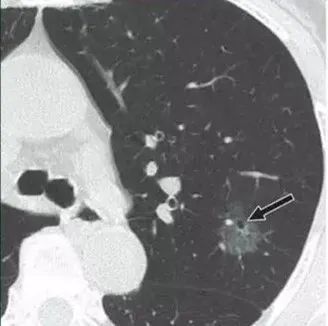

T影像学是肺部小结节的第一手资料。根据国家诊断指南,影像学医生首先将肺结节的肿瘤风险分为低风险结节(小于5mm)、中风险结节(5-8mm)和高风险结节(大于8mm)。当然,尺寸只是重要的参考标准之一,需要根据他们的“整体外观”等因素做出综合判断。如果它过于专业,就不会重复。

高危结节:随访3个月或选择穿刺活检和手术。最好进行影像学、胸外科、肿瘤学、呼吸系统、病理学等多学科会诊(MDT),以提供合理的治疗建议。一般而言,磨玻璃结节和亚实性结节患癌症的风险高于实性结节。早期癌症从非典型腺瘤性增生到原位癌再到微创腺癌的病理发展历史相对较长。因此,建议至少5年的随访期,这是测试“善与恶”的大师!还建议在同一家医院进行CT随访,以进行准确的影像学比较。在随访过程中,如果肺结节出现直径增大、密度增大、分叶、毛刺、胸膜凹陷等“不良”体征,则被列为高危结节,应及时到医院诊治。简言之,低剂量CT筛查癌症,早期发现和手术,将最大限度地为患者带来好处。